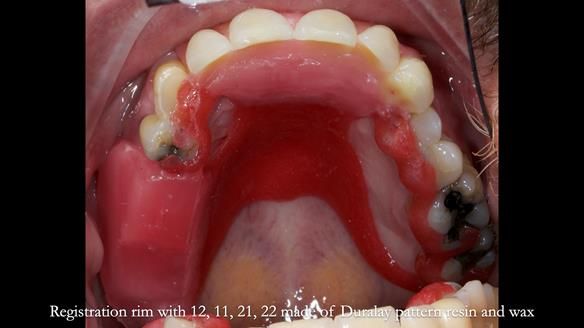

Keith’s combat denture case study

Keith’s case was one of the most challenging and rewarding cases I’ve treated this year. This 64 year old man presented with ill-fitting acrylic partial dentures that lacked stability, retention, and aesthetics. They constantly broke. He had lost the upper front teeth in a road traffic accident in his early 20s. The unopposed teeth had erupted, taking up space. After careful planning, we made a durable, metal-based upper partial denture/splint to address his dental concerns. He loved the outcome.

1. Denture design: A custom cobalt-chromium framework was Scandinavian-designed to maximise stability, protect the remaining teeth, and allow for future additions if needed.

Keith’s denture incorporated a Duracetal shell clasp on upper right first premolar (Myerson), which are designed to be virtually visible, providing a more aesthetic solution while enhancing patient comfort. The Scandinavian-inspired approach, based in modern removable prosthodontic techniques, ensured the denture was not only durable but also visually pleasing. Additionally, the design was carefully planned to allow for future modifications, ensuring that if Keith loses additional teeth, the denture can be adapted rather than replaced entirely.

I also used the Dahl concept to re-establish the occlusion upon fitting the RPD, which helped to intrude the lower left canine without needing to grind it too much.